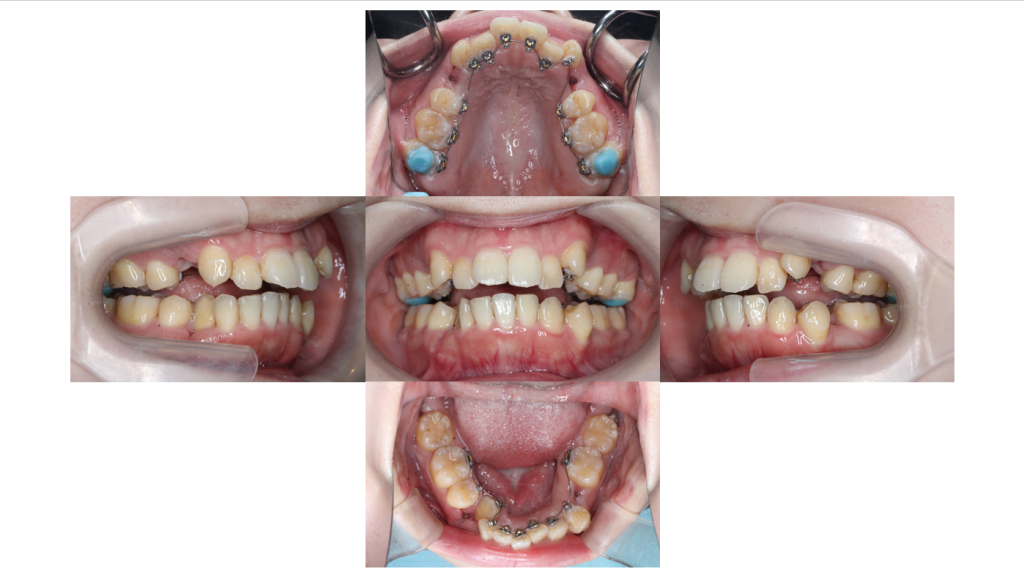

装置装着

叢生・裏側矯正の症例上下装置装着後の口腔内写真です。